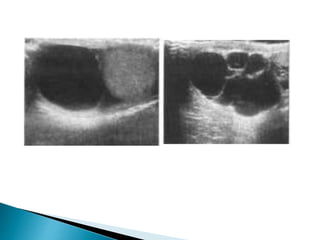

• #26 Ultrasound demonstration of a hydrocele seen as an echofree area partly surrounding a normal testicle

• #29 Ultrasound showing an infected, partly septated echogenic hydrocele

• #34 Ultrasound showing (A) a classical echo-free well-defined thin-walled solitary epididymal cyst and (B) a cluster of simple cysts.